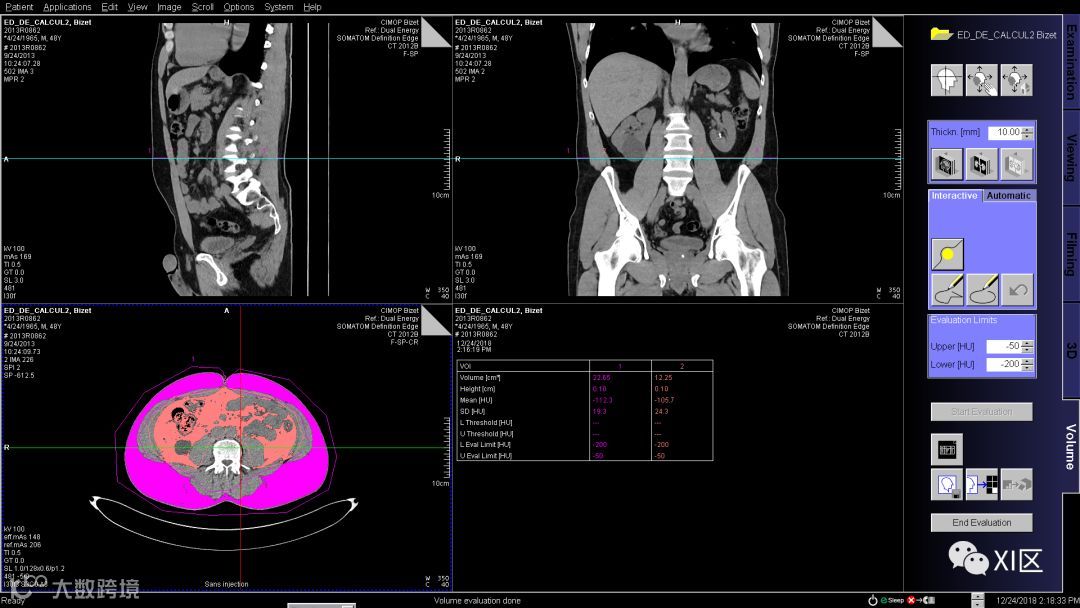

勾勒完成后如下图,修改评估阈值为-50到-200HU,然后单击开始评估获得结果。

再使用自由ROI工具将腹腔内的脂肪勾勒出来,点击开始评估,在右下像格即可获得腹壁和腹腔内脂肪的体积数据。